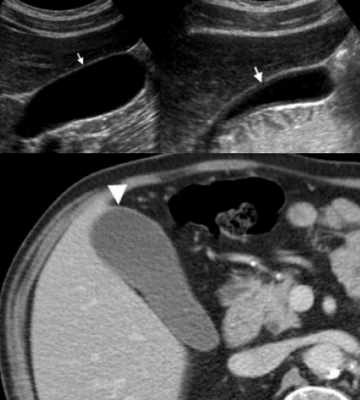

• УЗИ: гипоэхогенные узлы или тяжи в утолщенной стенке желчного пузыря:

о Желчные камни, сладж, эхогенные включения дебриса

(Слева) На аксиальной КТ с контрастным усилением у мужчины 75 лет без какой-либо симптоматики определяется иррегулярное утолщение стенки желчного пузыря с наличием в ней гиподенсных включений.

(Справа) На сонограмме у этого же пациента определяется асимметричное утолщение стенки желчного пузыря с наличием сладжа в его просвете и конкремента в области шейки. Визуализируется также участок неизмененной жировой ткани. Предоперационная дифференциальная диагностика рака желчного пузыря и ксантогранулематозного холецистита часто бывает сложной, однако отсутствие расширения желчных протоков позволяет предположить скорее хронический воспалительный процесс, а не новообразование.

5. УЗИ признаки ксантогранулематозного холецистита:

• Утолщение стенки желчного пузыря, в т.ч. (редко) очаговое и опухолевидное, имитирующее рак

• Гипоэхогенные узлы или тяжи в стенке желчного пузыря

• Повышение эхогенности перихолецистического жира (воспаление тканей около желчного пузыря, отражающих ультразвук)

• Желчные конкременты, сладж, эхогенные включения дебриса в просвете

• Перихолецистические включения жидкости

• Гипоэхогенные участки воспаления паренхимы печени возле ямки желчного пузыря

(Слева) На аксиальной КТ с контрастным усилением у мужчины 88 лет без какой-либо симптоматики, выполненной по поводу аневризмы аорты, определяется неравномерное утолщение стенки желчного пузыря с наличием в ней включений низкой плотности (случайная находка).

(Справа) На сонограмме у этого же пациента определяется утолщение стенки желчного пузыря с гипоэхогенными включениями в ней и наличием сладжа в просвете органа. При лапароскопической холецистэктомии подтвердился хронический ксантогранулематозный холецистит. При выраженном спаечном процессе и утолщении стенки в связи с хроническим воспалением часто возникает необходимость в открытой холецистэктомии.